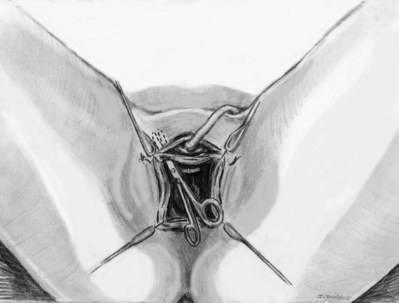

Stamey needles or large clamps are passed from above, through the abdominal incision by careful guidance behind the pubis, and passage is in contact with the pubis throughout until brought out lateral to the bladder and through the vagina (Fig. 73–5). Alternatively, large surgical instruments such as Tonsil clamps may also be used (McGuire, 1978; Blaivas and Olsson, 1988). The bladder must be completely drained before passage of the Stamey needles to avoid inadvertent bladder injury. Cystoscopy should be performed with a 70-degree lens after passage of the needles to confirm the integrity of the bladder, by following the course of the needles (while an assistant moves them). Cystoscopy is not practiced consistently by all urologists after needle passage except when there is visible hematuria or another cause for suspicion (Niknejad et al, 2002; Seung-June et al, 2007). It is the authors’ belief that this step eliminates the morbidity and reoperation required for passage of the sling through the bladder and that cystoscopy is an essential step. In the case of a small bladder injury or inadvertent passage of Stamey needles through the bladder, the needles are removed and passed again and the procedure is completed. Extravesical passage is confirmed. One ampule of indigo carmine is given at this point to confirm ureteral efflux during final cystoscopy for tensioning of sling. The Foley catheter is replaced. The ends of graft suture are passed through the Stamey needle eyelets. After marking the center of the graft with a clamp, the Stamey needles are removed and the ends of the suture are brought out through the abdominal incision and tagged with hemostat clamps (Figs. 73-6 and 73-7). The distal aspect of the graft is sutured to the periurethral tissue with two simple 4-0 polyglactin sutures. The vaginal incision is closed with a watertight, running 2-0 polyglactin suture after complete hemostasis is achieved. Before final tensioning of the sling (see Fig. 73-7) the vagina should be closed and the weighted speculum removed to eliminate factors that can affect the final tension. The polydioxanone sutures are tied down above the rectus fascia (see Fig. 73–7) while cystoscopy with a 30-degree lens is performed to visualize adequate coaptation of the proximal urethra. There is approximately a two-fingerbreadth width between the rectus fascia and the sutures once tied down. The amount of tension may vary owing to the mobility of the urethra or desire to create permanent retention in an individual who will have permanent catheterization. The abdominal incision is closed with a subcuticular 4-0 polyglactin suture. The Foley catheter is left to straight drainage, and a vaginal pack moistened with conjugated estrogens is placed.